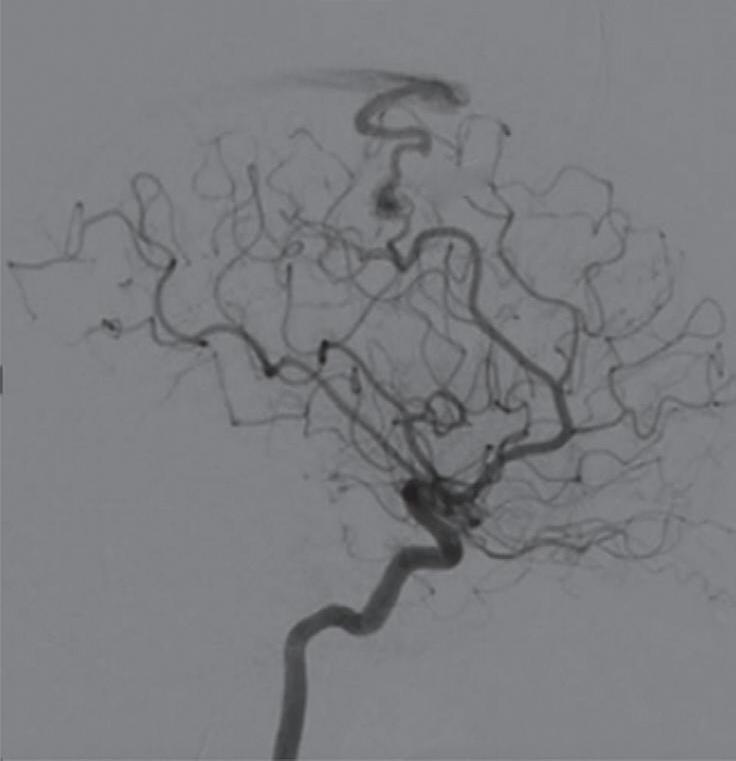

Com relação ao fluxo no interior do nidus, alguns autores classificam-nas em alto fluxo (Fig. 1-8) e baixo fluxo (Fig. 1-9). São consideradas de alto fluxo aquelas em que a opacificação após injeção de contraste ocorre apenas na malformação, em contrapartida, nas de baixo fluxo, ocorre opacificação da MAV e de outras artérias normais do mesmo território vascular. Exemplificando as lesões de alto fluxo temos as malformações arteriais, as malformações arteriovenosas e as fístulas arteriovenosas, enquanto as lesões de baixo fluxo são representadas pelas malformações venosas, linfáticas e capilares.25

Fig. 1-8. (a-c) RNM T1 com contraste, cortes sagital (a), coronal (b) e axial (c) demonstrando MAV não rota com nidus localizado no lobo occipital à esquerda (setas longas). (d) Arteriografia digital cerebral com injeção de contraste via carótida direita (AP) mostrando a contribuição da carótida direita na irrigação da MAV contralateral. (e,f) Com injeção de contraste via carótida esquerda, em Perfil e AP respectivamente, observa-se nidus compacto nutrido por ramos da artéria cerebral média à esquerda e a veia de drenagem precoce se dirigindo para o seio sagital superior. Projeções em AP (g) e em perfil (h) demonstrando a contribuição do sistema vertebrobasilar por meio de ramos distais da artéria cerebral posterior à esquerda e drenagem para os seios sagital superior e sigmoide à esquerda (setas curtas).